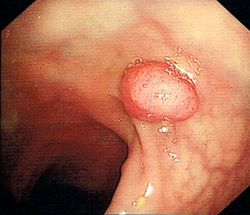

大腸癌是本港第3常見的癌症,亦是本港致命癌症中的第2位。大腸癌篩查可及早識別未出現病徵的大腸癌患者或高危人士,讓其及早接受治療,大大提高治癒率,而在大腸鏡檢查過程中切除大腸腺瘤,則可避免腺瘤演變成癌症。經計劃確診大腸癌的個案中,約2400宗已進行初步分析,結果顯示約56%屬於早期個案,治癒率較高。